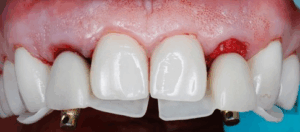

Not all clinical situations present us with ideal immediacy outcomes and staging may be the only option. The following case presented with initial plan extract teeth and immediately place implants with immediate fixed temporary. Due to lower stability at implant #7, we decided to avoid temporalization until at least 2 mo post implant placement.

Immediate implants were placed and patient was given an Essix retainer to wear for at least 6 weeks post implant placement.

Once the temporary is picked up and emergence profile is customized to have an adequate regenerative space and properly placed Critical contour (0.5 short of the final gingival margin) we are ready to deliver the prosthesis.

Prior to delivery make sure to leave a good amount of room in the embrasures to allow for soft tissue fill during the training period.

Upon delivery of the prosthesis, some blanching is a good sine of tissue compression in needed areas (usually proximally) which starts the process of tissue training.